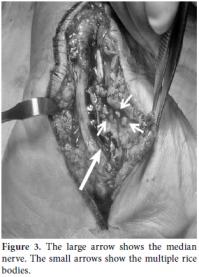

A 48-year-old male was treated at another health center for a year due to painless swelling over the volar region of the left wrist. He also had paresthesia and numbness in the median nerve distribution of the hand and forearm before coming to our clinic. There were no constitutional symptoms or past history of major illness, but he was known to be an alcoholic. Surgery had been performed twice by the primary physician at the other clinic based on a misdiagnosis of a volar wrist ganglion. A physical examination revealed non-tender, fluctuant swelling over the volar aspect of the left wrist. The overlying skin appeared normal, and there was limited flexion of the wrist joint. The swelling extended through the carpal tunnel and ended at the mid-palm. Plain radiographs of the wrist and chest were normal, and laboratory findings, which included the erythrocyte sedimentation rate (ESR), were within normal limits. Magnetic resonance imaging (MRI) of the left wrist revealed tenosynovitis of the flexor digitorum superficialis and profundus. It was decided that surgical intervention via a synoviectomy was the best course of action because of the swelling around the tendon sheaths. A classic, lengthened carpal tunnel incision was performed which allowed for the decompression of all of the affected tendon sheaths (Figure 1). At the beginning of the operation, a swollen capsular mass was detected on the proximal edge of the wound that mimicked volar wrist ganglia. The capsule was opened, the cold abscess-like fluid drained, and rice bodies were detected. The swollen capsular mass was suspected to be a part of tuberculous tenosynovitis (Figures 2 and 3). Afterwards, a complete tenosynovectomy with extensive debridement of the surrounding granulation tissue and carpal tunnel decompression was performed (Figure 3), and the wound was then primarily closed. Mycobacterium tuberculosis was isolated on a culture, and a histopathological examination revealed caseous necrosis with granuloma formation (Figure 4). The patient received anti-TB chemotherapy for nine months, which included ethambutol, pyrazinamide, rifampicin, and isoniazid for the first three months and only isoniazid and rifampicin for the next six months. Follow-up examinations were conducted at two month intervals, and at two years postoperatively, the patient was found to be symptom free, with full range of motion in the wrist joint. No recurrence was detected.